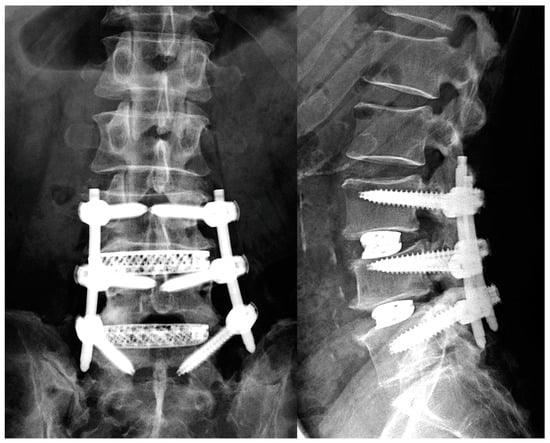

Extreme lateral interbody fusion (XLIF) [] has become widely used because of its strong corrective force and minimally invasive nature (Figure 1). The corrective force of XLIF is driven by the scaffolding of the cage on the sturdy portion of the vertebral endplate, which depends on the support of the undamaged vertebral endplate. An important complication of XLIF is cage subsidence, which can lead to clinical problems, such as loss of disc height compensation, loss of spinal alignment, recurrent pain, and vertebral fractures []. Once the endplates are injured, the correction force of the cage is at least partially lost, and the patient is at risk of further subsequent subsidence and the worsening of clinical improvement []. Therefore, it is critical that the vertebral endplate not be injured during XLIF cage insertion.

Figure 1. Lumbar degenerative spondylolisthesis treated by 3DTi cage and PPS.